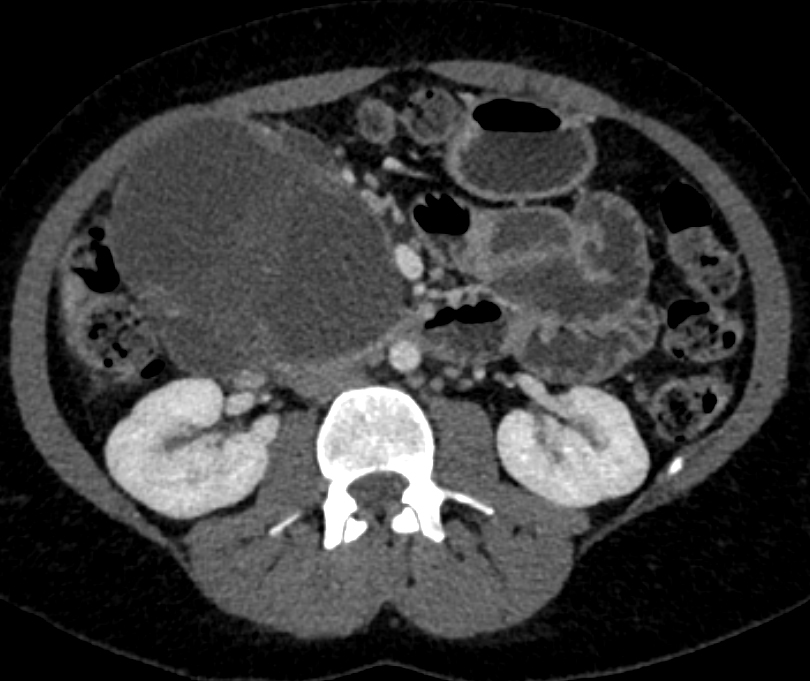

3) The most likely diagnosis in this 45 year old female is?

serous cystadenoma

mucinous cystic neoplasm (MCN)

IPMN

SPEN tumor